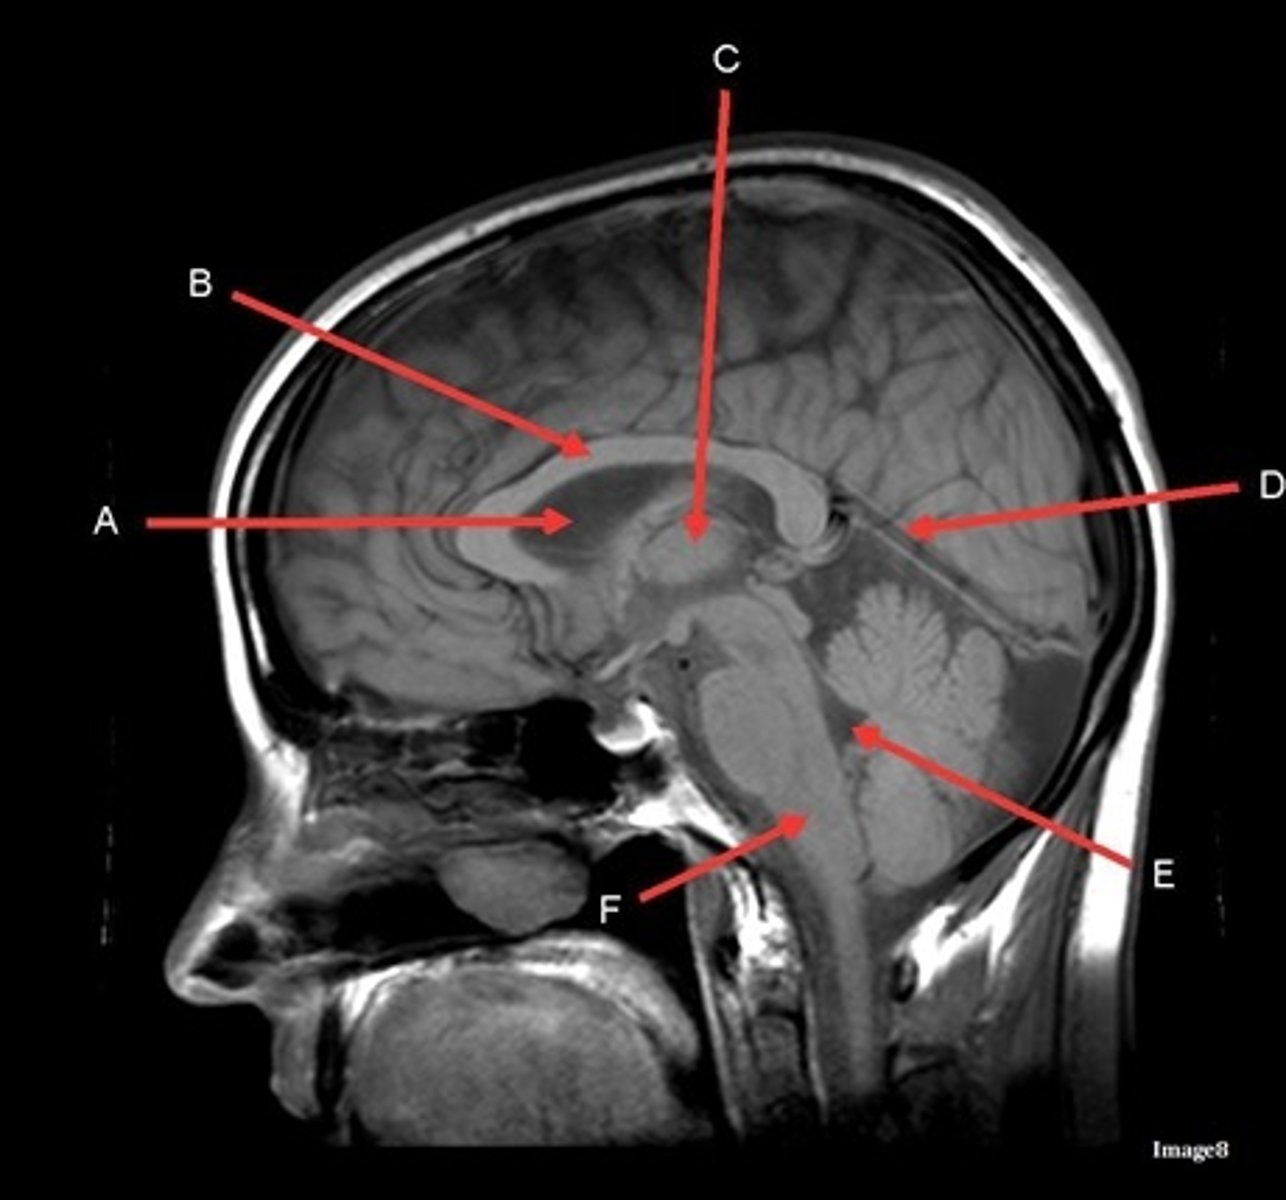

What type of sequence?

T1, sagittal

A

lateral ventricle

B

corpus callosum

C

thalamus

D- separates what

tentorium cerebelli- cerebrum (occipital and temporal lobes) from brainstem and cerebellum

E

fourth ventricle

F

medulla oblongata